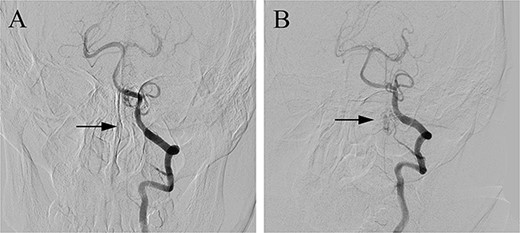

(A) Preoperative head CT, (B) CTA and (C, D) DSA identified the fistula (arrows) in the left lateral dural membrane and confirmed the intradural origin of the drainage vein.

Postoperative DSA (A) confirmed the complete occlusion of the fistula (arrow) when compared with the preoperative DSA (B).